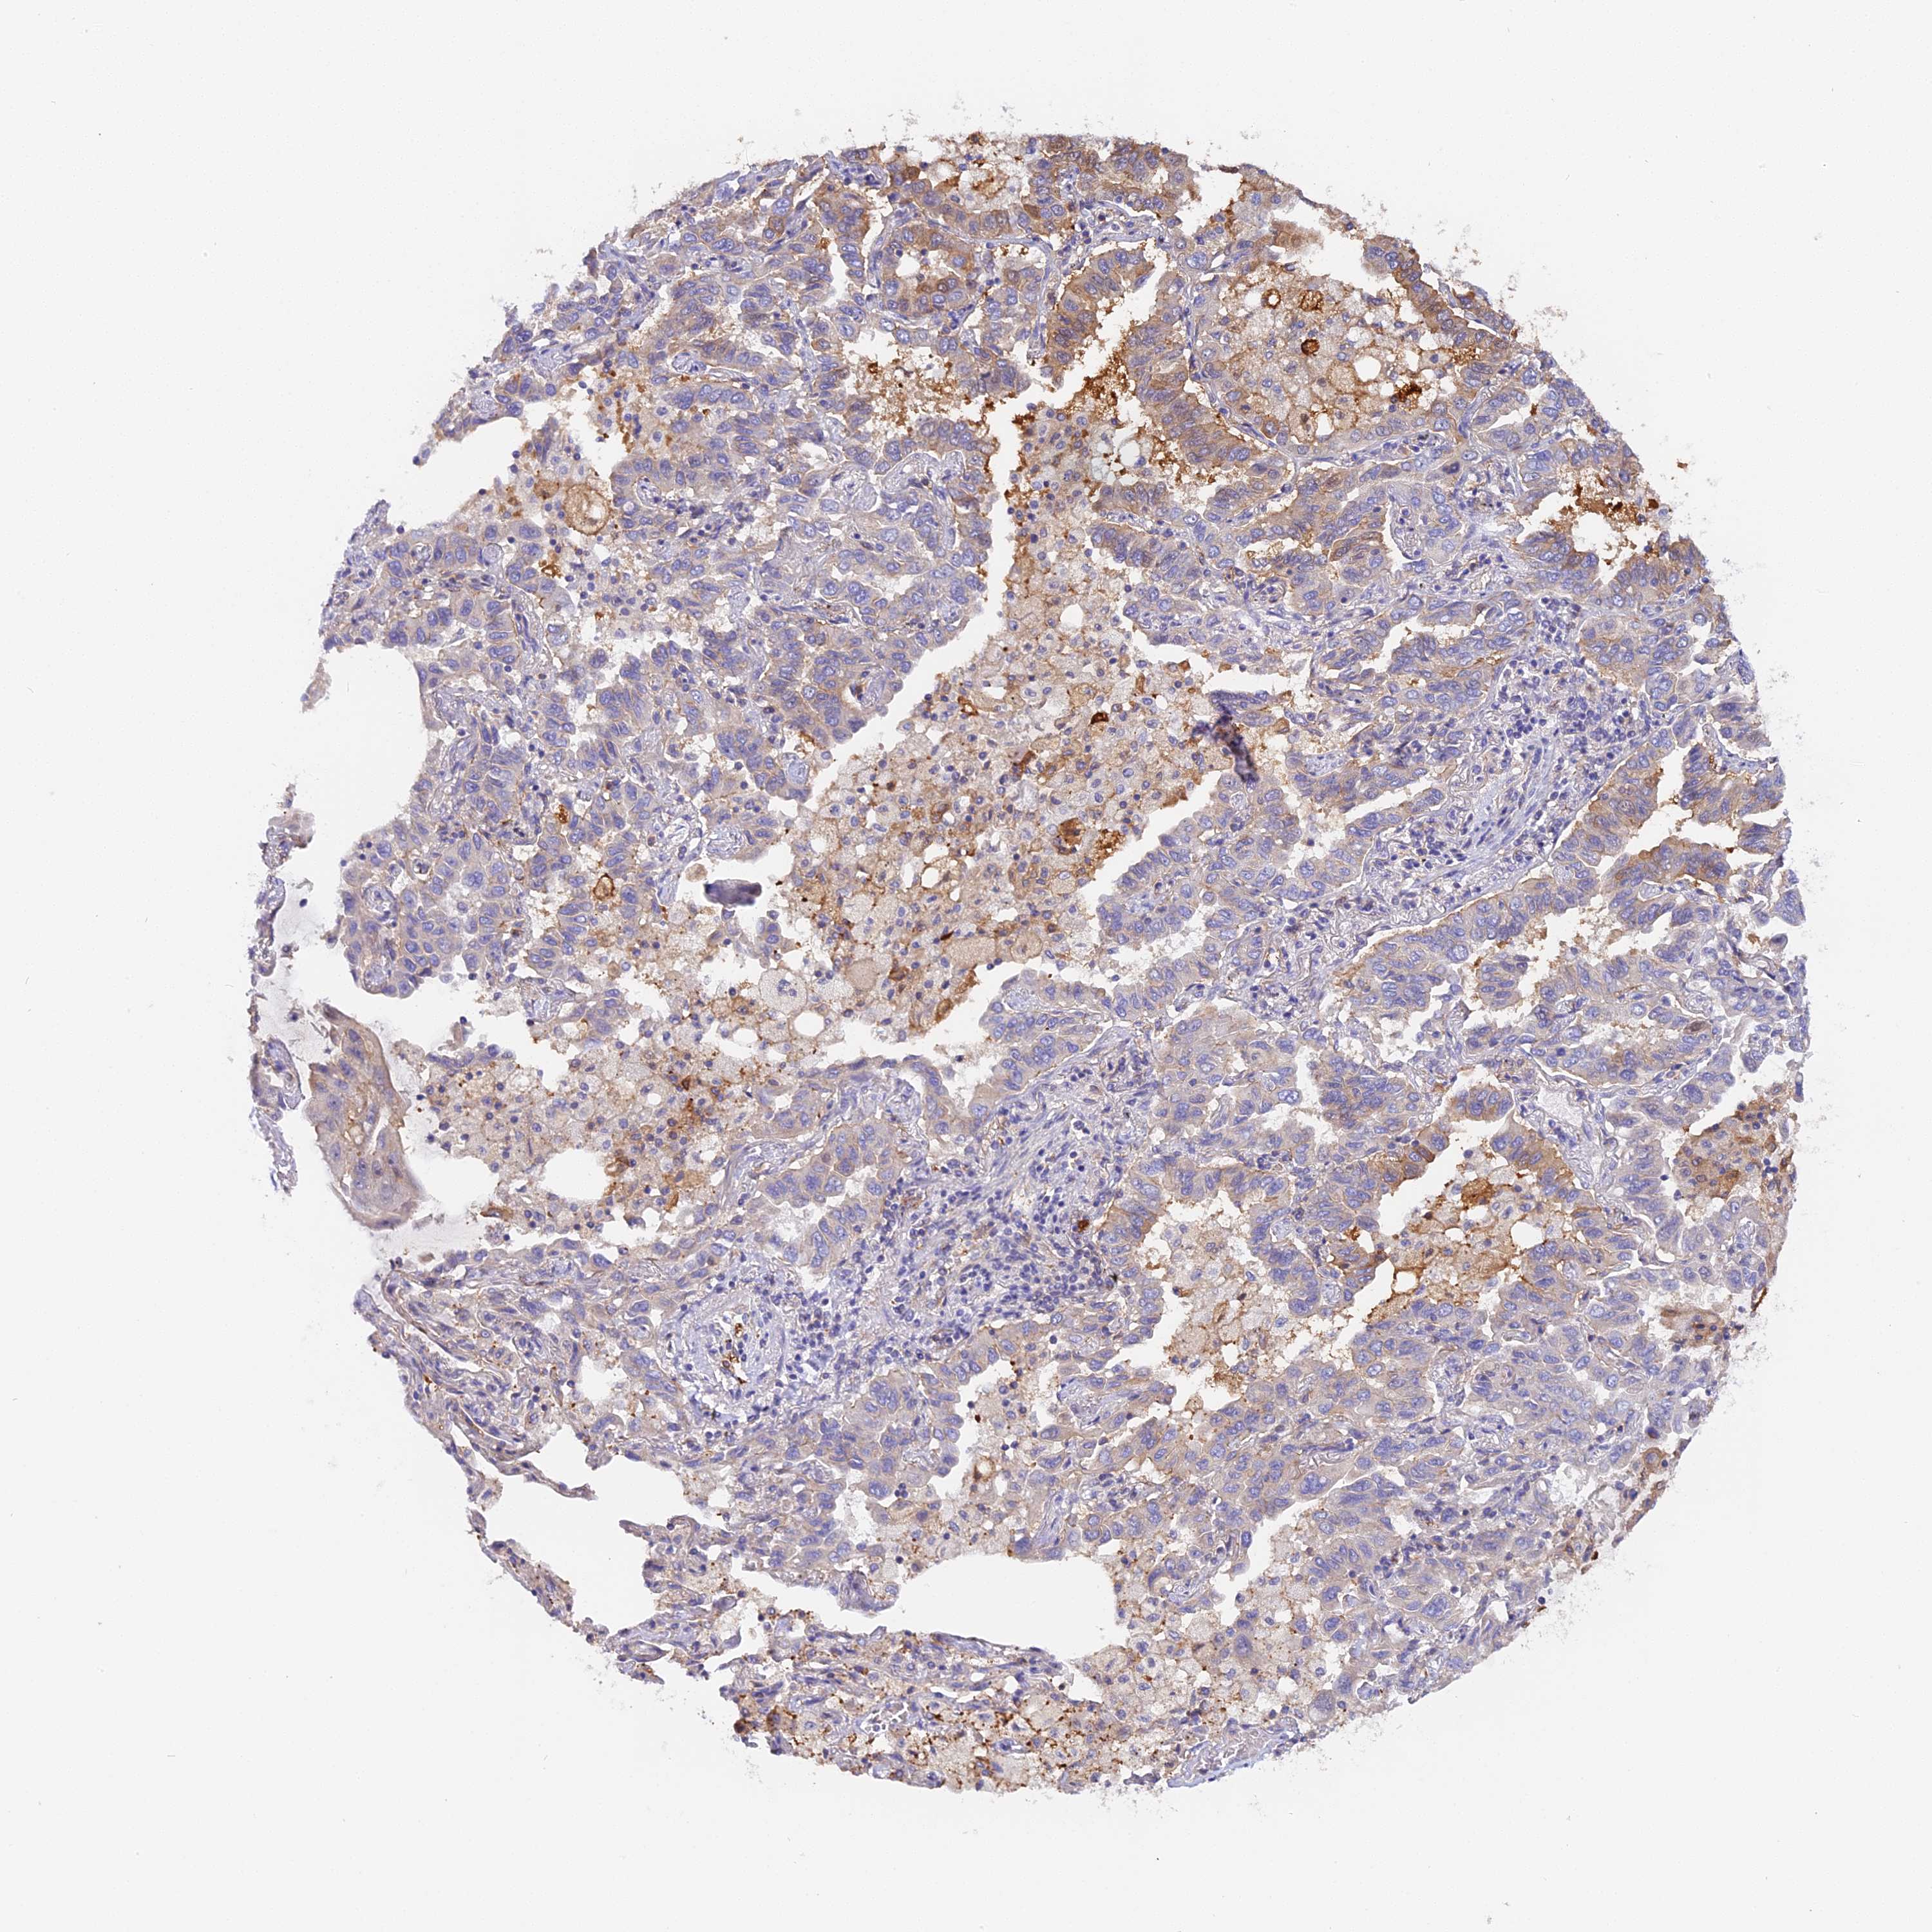

LUNG SQUAMOUS CELL CARCINOMA (TCGA) - Interactive survival scatter ploti

The Survival Scatter plot shows the clinical status (i.e. dead or alive) for all individuals in the patient cohort, based on the same data that underlies the corresponding Kaplan-Meier plots. Patients that are alive at last time for follow-up are shown in blue and patients who have died during the study are shown in red.

The x-axis shows the expression levels (FPKM) of the investigated gene in the tumor tissue at the time of diagnosis. The y-axis shows the follow-up time after diagnosis (years). Both axes are complimented with kernel density curves demonstrating the data density over the axes. The top density plot shows the expression levels (FPKM) distribution among dead (red) and alive patients (blue). The right density plot shows the data density of the survived years of dead patients with high and low expression levels respectively, stratified using the cutoff indicated by the vertical dashed line through the Survival Scatter plot. This cutoff is automatically defined based on the FPKM cutoff that minimizes the p-score. The cutoff can be changed by dragging the vertical line or by entering a cutoff value in the square labeled "Current cut-off".

Under the Survival Scatter plot the p-score landscape (black curve; left axis) is shown together with dead median separation (red curve; right axis). Dead median separation is the difference in median mRNA expression between patients who have died with high and low expression, respectively. It is calculated as follows: median FPKM expression of dead patients with high expression - median FPKM expression of dead patients with low expression. This is intended to aid the user in visually exploring custom cutoffs and the associated p-scores and dead median separation.

Individual patient data is displayed and can be filtered by clicking on one or more of the category buttons on the top of the page. Categories describing expression level and patient information include: high, low, alive, dead, female, male and tumor stages. The scale of the x-axis can be toggled between linear and log-scale by clicking on the "x log" button. Mouse-over function shows TCGA ID, patient information and mRNA expression (FPKM) for each patient.

& Survival analysisi

Kaplan-Meier plots summarize results from analysis of correlation between mRNA expression level and patient survival. Patients were divided based on level of expression into one of the two groups "low" (under cut off) or "high" (over cut off). X-axis shows time for survival (years) and y-axis shows the probability of survival, where 1.0 corresponds to 100 percent.

KATNB1 is not prognostic in Lung Squamous Cell Carcinoma (TCGA)

: 16.22

Average pTPM 20.3

Number of samples 489